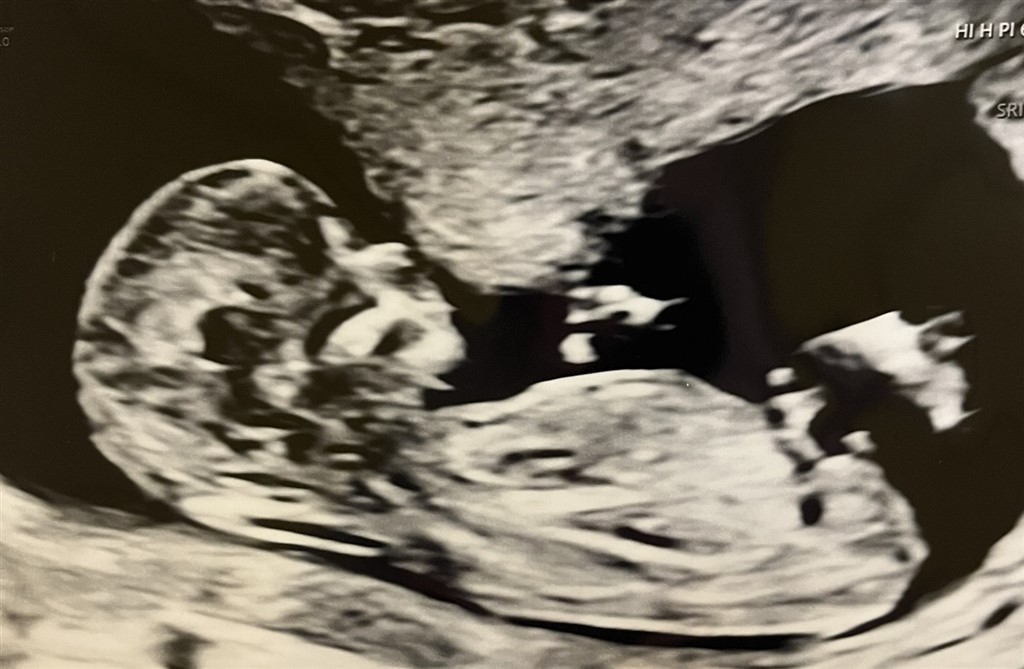

Jeg er 13+3 i dag og synes, at jeg til scanningen så en tydelig tissemand. Er vi enige om, at det her ligner en dreng mistænkelig meget?

Vedhæftede fotos (klik for at se i fuld størrelse)

Jo, jeg vil med 100% sikkerhed også sige dreng